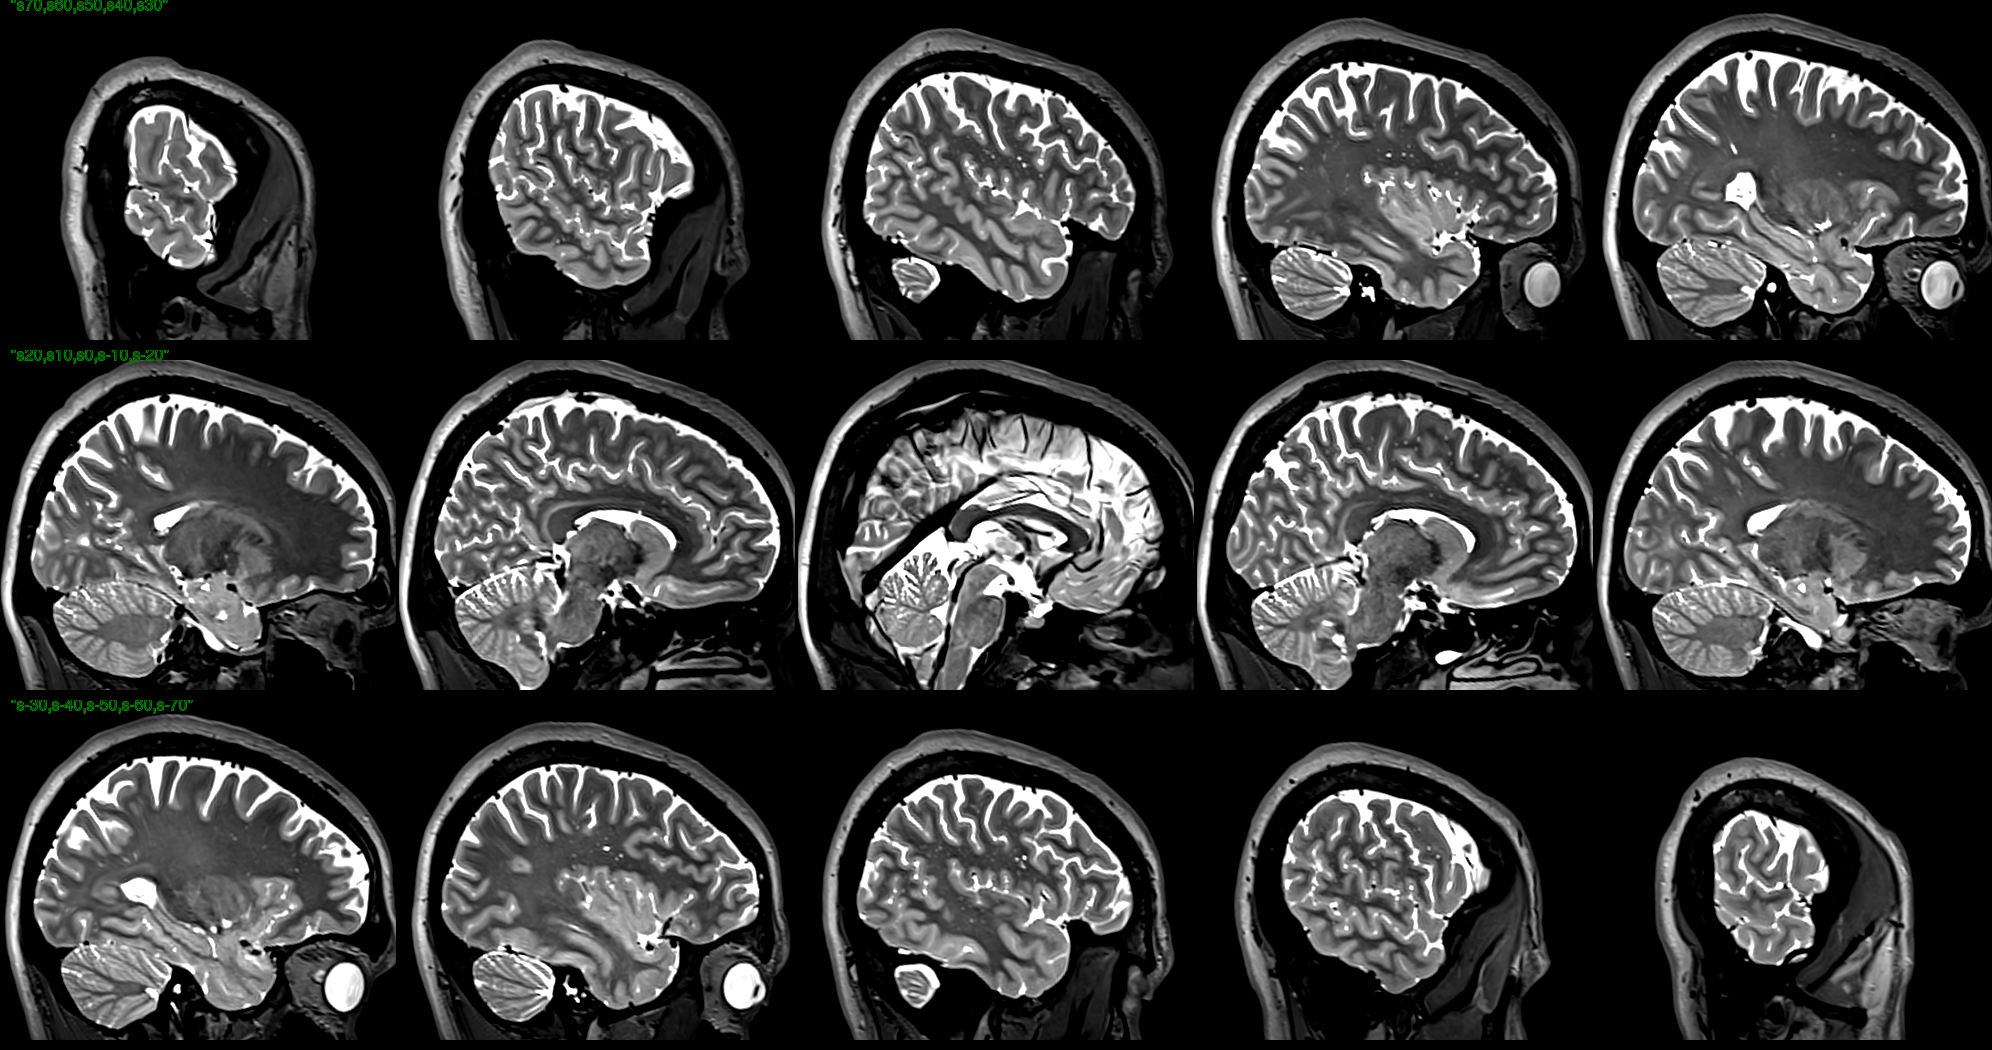

T2 images